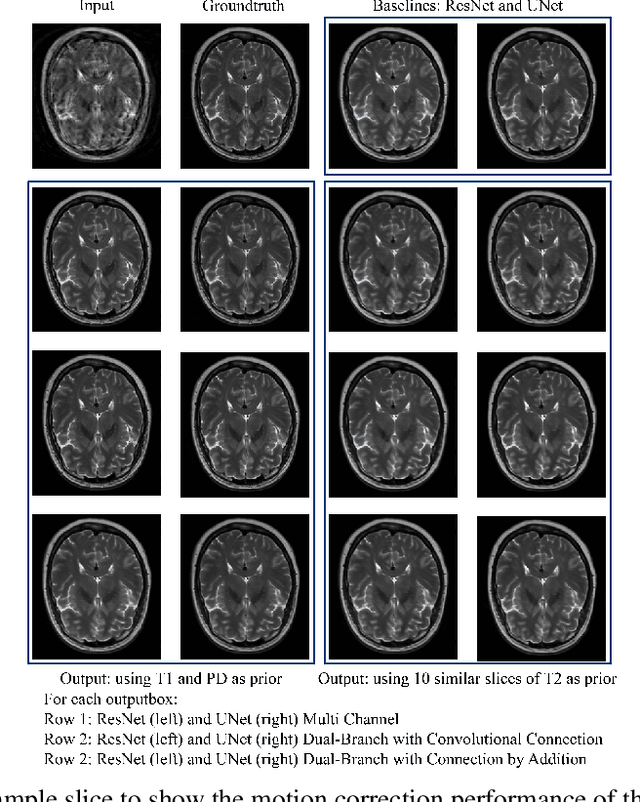

Abstract:In MRI, motion artefacts are among the most common types of artefacts. They can degrade images and render them unusable for accurate diagnosis. Traditional methods, such as prospective or retrospective motion correction, have been proposed to avoid or alleviate motion artefacts. Recently, several other methods based on deep learning approaches have been proposed to solve this problem. This work proposes to enhance the performance of existing deep learning models by the inclusion of additional information present as image priors. The proposed approach has shown promising results and will be further investigated for clinical validity.